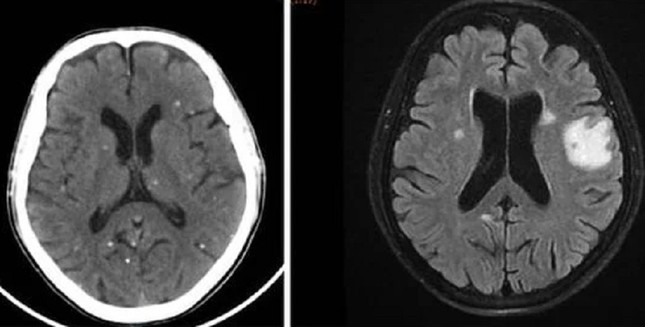

Sán làm tổ chi chít khắp cơ thể vì món khoái khẩu nhiều người Việt 'nghiện' - Ảnh 1.

Nang sán dải ký sinh ở bán cầu não hai bên là nguyên nhân khiến người bệnh bị tổn thương não, biểu hiện như đột quỵ

TS.BS Trần Thanh Hùng, Phó khoa Nội Thần kinh Tổng quát, Bệnh viện Nhân Dân 115 cho biết, qua thăm khám và chẩn đoán hình ảnh ghi nhận, người bệnh có tổn thương não nhiều vị trí, phù não. Kết quả xét nghiệm huyết thanh học cho thấy, bệnh nhân dương tính với ấu trùng sán dải lợn (Cysticercus).